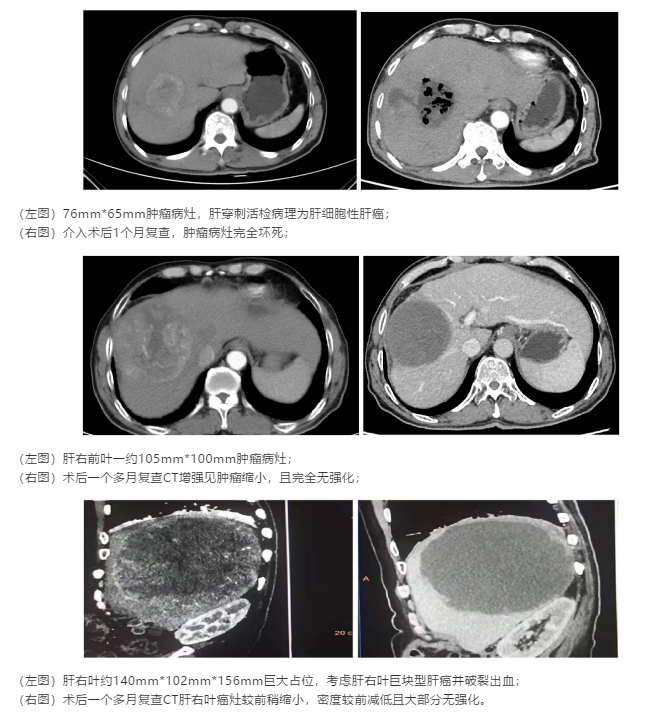

据统计,2020年8月-2021年1月,茂名市人民医院肿瘤一科共为29名中晚期肝癌病人了施行载药微球经肝动脉栓塞化疗术(DEB-TACE)(回访数据统计至2021年4月25日),29人中3个月疾病缓解率(CR+PR)为82.7%,疾病控制率(CR+PR+SD)为89.6%;6个月(12人满足6个月随访)疾病缓解率(CR+PR)为70%,疾病控制率(CR+PR+SD)为82%。与传统的碘化油栓塞化疗相比,载药微球栓塞化疗技术大大提高了中晚期肝癌病人的治愈率及明显减少介入手术次数。据肿瘤一科主任林华明介绍,这项技术使得部分中晚期肝癌病人明显获益,比如来自茂南区的74岁李伯、72岁的任伯以及来自电白区的58岁胡伯3例患者,经予DEB-TACE术治疗后,半年内多次复查结果显示,均实现了肿瘤继续缩小,疗效评估为CR或者PR。